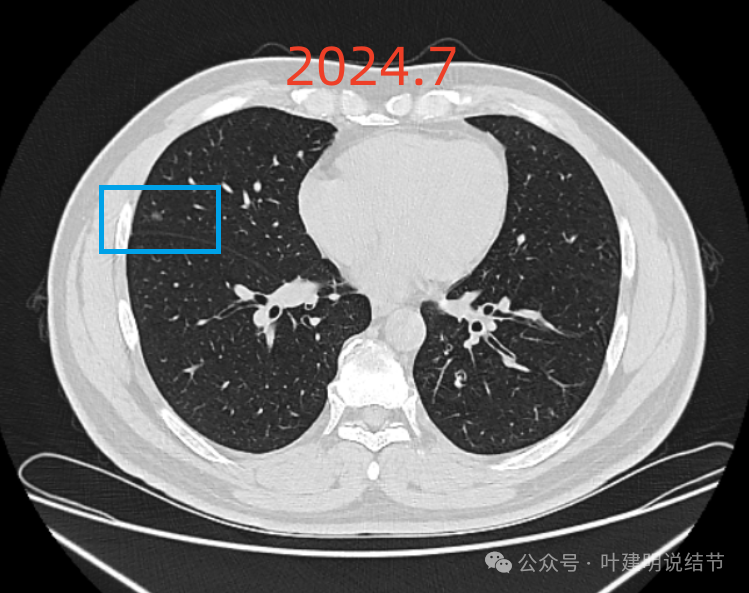

患者2019年7月体检首次发现右肺2处磨玻璃,大小5毫米,某医科大学附属第一医院随访4年,2024年7月复查右肺散在磨玻璃,和2023年12月份复查变化不大。备注:父亲肺癌晚期去世。辅检:23-12-10肺CT诊断结论 右肺散在磨玻璃结节,较大两枚高危倾向,对比2023-04-02CT部分新增,建议密切复查。两肺增殖钙化灶。24-7-14肺CT诊断结论左肺下叶细支气管炎,请结合临床及复查。右肺散在磨玻璃结节,对照2023-12-10CT大致相仿,建议定期复 查。两肺少许增殖钙化灶。今为咨询特来就诊。

右中叶病灶也与2022年5月比并无进展,而且小而稳定,也没有实性成分。

1、结节性质:右肺中叶以及下叶磨玻璃密度结节,整体轮廓清楚,瘤肺边界清,随访持续存在,是要考虑肿瘤范畴的。我分别截图了2022年5月、2023年12月以及2024年7月的最明显层面,两处病灶均基本没有任何变化进展。而且灶内并无实性成分,应该考虑肺泡上皮增生或不典型增生可能性为大,但由于影像表现存在交叉,纯磨既可以是前面我说的这两者,也可以是原位癌或微浸润性腺癌,甚至浸润性腺癌贴壁型也会是这样的表现,但不管最后是什么,只要纯磨密度风险就是低的,随访不至于延误病情,也不会有不同预后,都是局部完整切除就治愈。